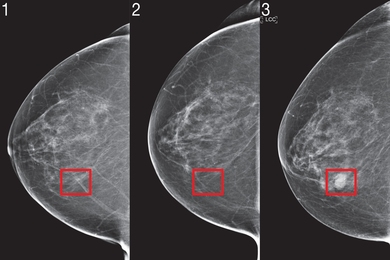

پزشکان مجارستانی در حال حاضر از هوش مصنوعی‌ای استفاده می‌کنند که می‌تواند سرطان پستان را تا چهار سال پیش از گسترش کامل تشخیص دهد.

به گزارش کاماپرس، این فناوری که با عنوان تشخیص با همکاری رایانه شناخته می‌شود، با برجسته‌کردن مناطقی روی جواب آزمایش ماموگرافی به پزشکان کمک می‌کند که بررسی و آزمایش‌های دقیق‌تری را انجام دهند.

تحقیقاتی از دانشگاه ام‌آی‌تی نشان می‌دهد که هوش مصنوعی می‌تواند تغییرات بین ماموگرافی‌ها و نقاط کوچکی را که در خطر تبدیل به غده‌های سرطانی هستند، تشخیص دهد. این مناطق طی زمان درنهایت تبدیل به سرطان پستان می‌شوند.

آزمایشگاه علوم رایانه‌ای و هوش مصنوعی ام‌‌آی‌تی این الگوی ژرف را با استفاده از داده‌های بیش از 90هزار جواب آزمایش ماموگرافی در بیمارستان ماساچوست ایجاد کرده‌اند. این الگو نمونه‌های نامحسوس و مبهم را که برای چشم انسان دشوار است، در بافت‌های پستان تشخیص می‌دهد.

این الگوی هوش مصنوعی، براساس جواب‌های ماموگرافی و نتایج تحقیق روی بیش از 60 هزار بیمار، شاخص‌های اولیه سرطان را تشخیص داده و می‌تواند احتمال گسترش سرطان پستان را در آینده برای بیمار پیش‌بینی کند.